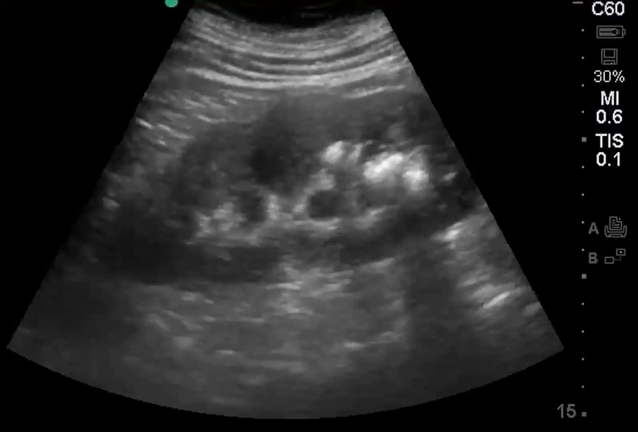

Abdominal Ultrasound

- Extended normal anatomy: liver, gallbladder, pancreas, spleen, kidneys, pelvis, large vessels and bowel